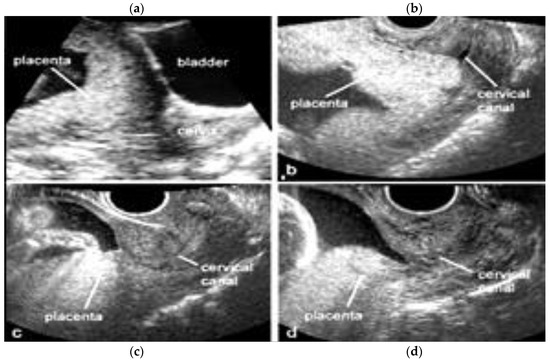

3.1.2. Placenta Praevia

3.2.2. Vasa Praevia